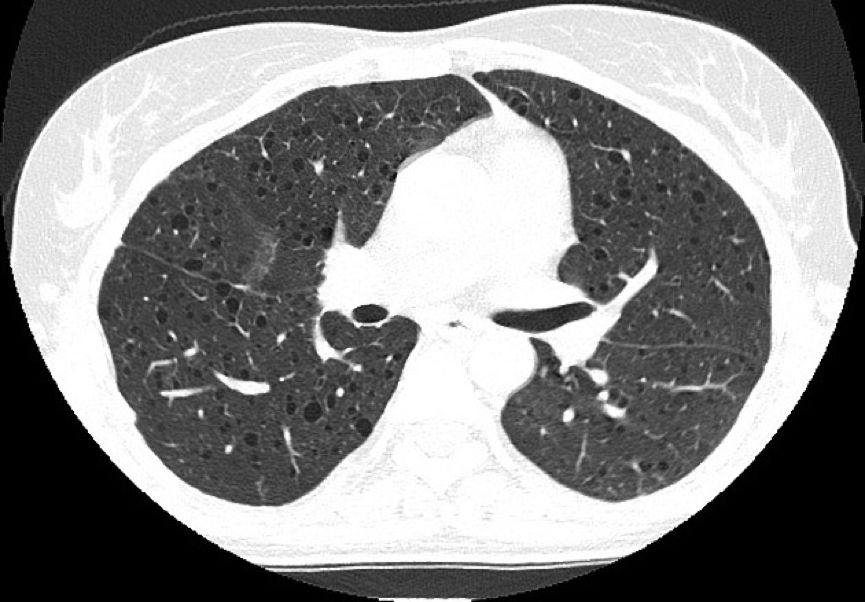

外院肺功能检查提示:阻塞性通气功能障碍。HRCT显示双肺弥漫性分布类圆形薄壁囊状阴影,囊壁较光滑,囊腔大小不等,多数在2~10 mm之间,右侧胸腔内见气体影。纵隔结构清楚,未见肿大淋巴结。

常规CT表现为两肺密度减低,体积增大,呈肺气肿样改变。HRCT对本病的早期诊断及病情发展的监测有重要意义,其特征性改变为两肺广泛弥漫性分布的薄壁小囊状病变,两侧对称,无上中下肺野的区别,也无中央性与周围性的分布差异。囊腔直径为2~30 mm,大多数直径小于10 mm,囊壁厚度多小于2 mm。

中年女性反复发生气胸及出现原因不明的呼吸困难、咯血或乳糜胸时,应疑诊是否有PLAM,当HRCT示双肺散在、多发薄壁囊腔时,一定要想到PLAM的可能性。